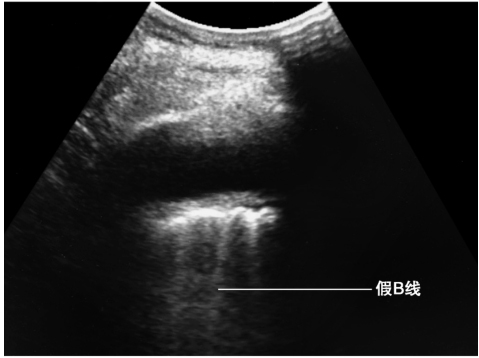

(2)B征象

B线是起自胸膜线与之垂直地随肺滑动而运动的高回声亮线,伴有“彗星尾”征,反映了其周边肺组织内的特殊的“液-气混合状态”,同一切面出现3条以上B线提示肺间质综合征的存在(图3)。因为肺炎病灶在肺内往往并不呈对称分布,因此可以表现为肺叶之间或同一肺叶内部不同区域分别存在B征象和A线(即残留有正常肺组织的区域)。需要注意的是,当有胸腔积液时,类似的高回声亮线起自肺表面,该伪像称为假B线,并不能作为反映肺实变的可靠依据(图4)。

图4 假B线